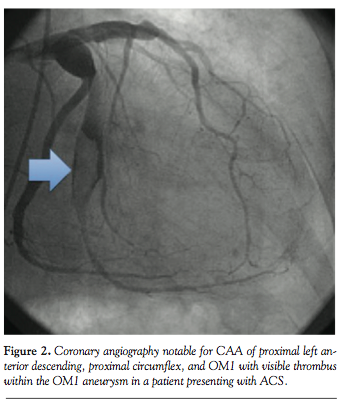

Case 2. An 85-year-old man with past medical history of dyslipidemia and atrial fibrillation on chronic warfarin therapy presented with unstable angina. Angiography revealed a dominant left circumflex with aneurysmal dilatation proximal to the bifurcation with the first obtuse marginal branch (OM1). OM1 was large in caliber, with a proximal, thrombus-filled aneurysm (Figure 2) with TIMI-2 flow distally. A CAA was also noted in the proximal LAD with the remainder of the left coronary artery having only mild CAD. The right coronary artery (RCA) was small and non-dominant. Left ventriculography

demonstrated an ejection fraction of 20% with severe hypokinesis of the lateral and anterolateral walls. After extensive discussion, the patient declined invasive therapy and elected to proceed with conservative management. IV unfractionated heparin and IV eptifibatide were continued for 48 hours. Atorvastatin, carvedilol, and lisinopril were maximized and warfarin was restarted at discharge with a LMWH bridge, both for paroxysmal atrial fibrillation and thrombosed CAA. He has done well throughout follow-up.